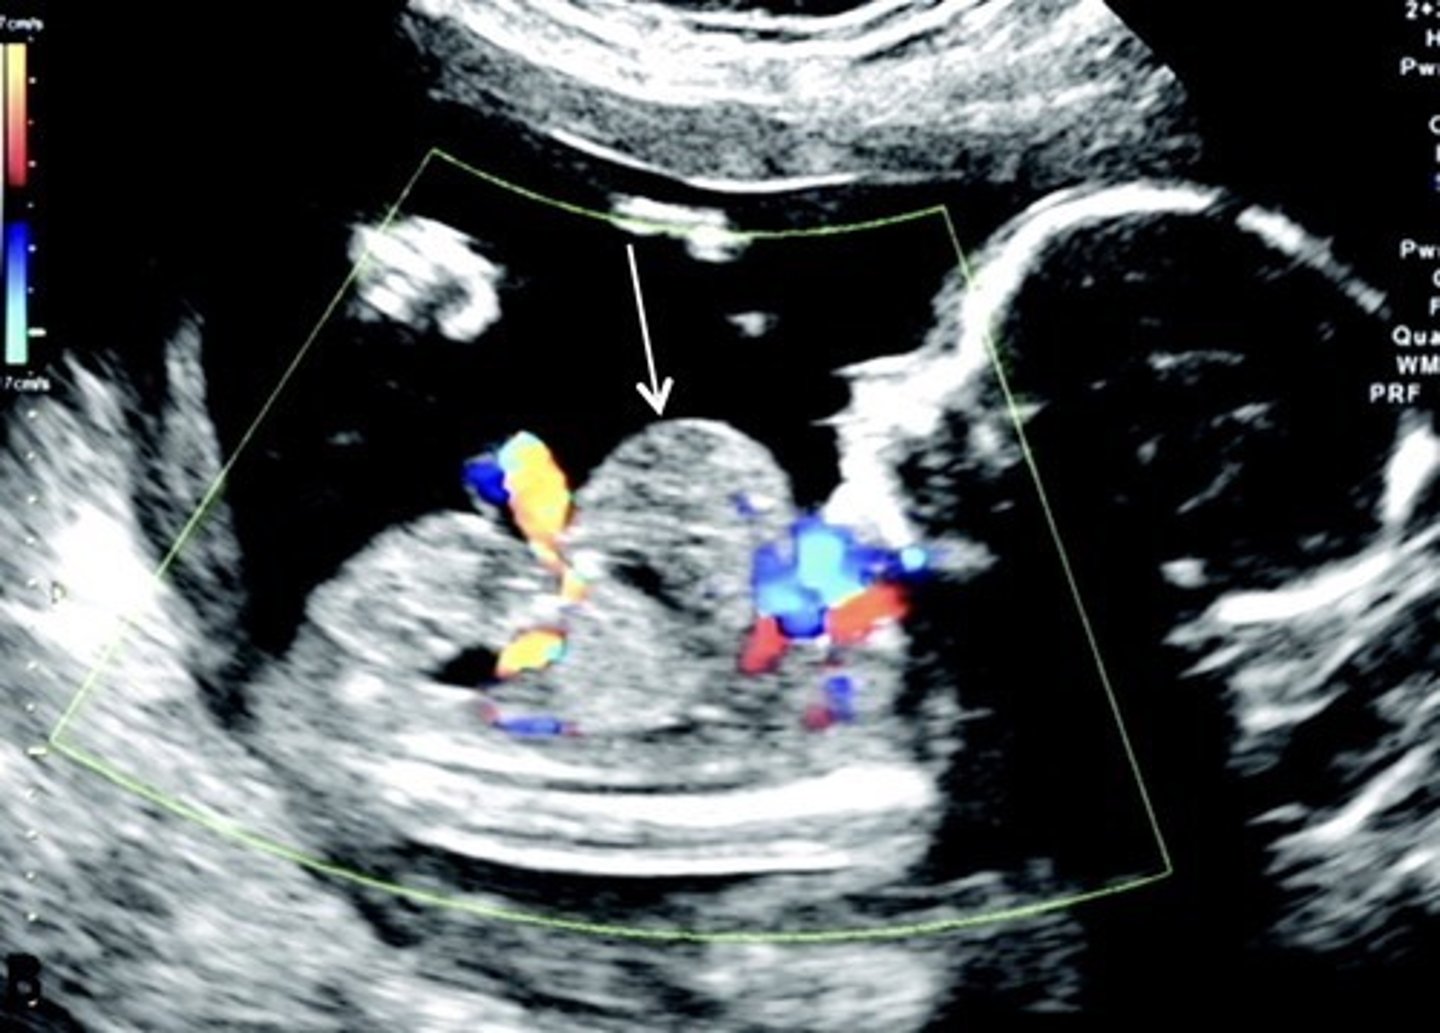

Duodenal Atresia

Fluid reaches duodenum, but cannot move past it

Double Bubble Sign

Enlarged stomach & prox. duodenum